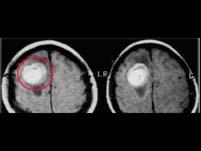

急性放射性反应包括()A.放射性脑水肿B.放射性皮炎、中耳炎C.放射性脑坏死D.恶心、呕吐E.脱发

问题 急性放射性反应包括()

选项 A.放射性脑水肿 B.放射性皮炎、中耳炎 C.放射性脑坏死 D.恶心、呕吐 E.脱发

答案 ABDE